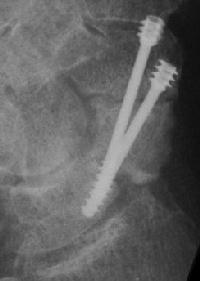

Case 7. This nonunion patient's scaphoid and iliac crest were unusually soft bone.

Click for larger image

After two screws, the fixation was clearly inadequate, so I put a third screw through the graft into the proximal pole. I wasn't sure whether to buy

stock in Herbert screws or Zantac. The fracture healed despite AWOL and no immobilization.